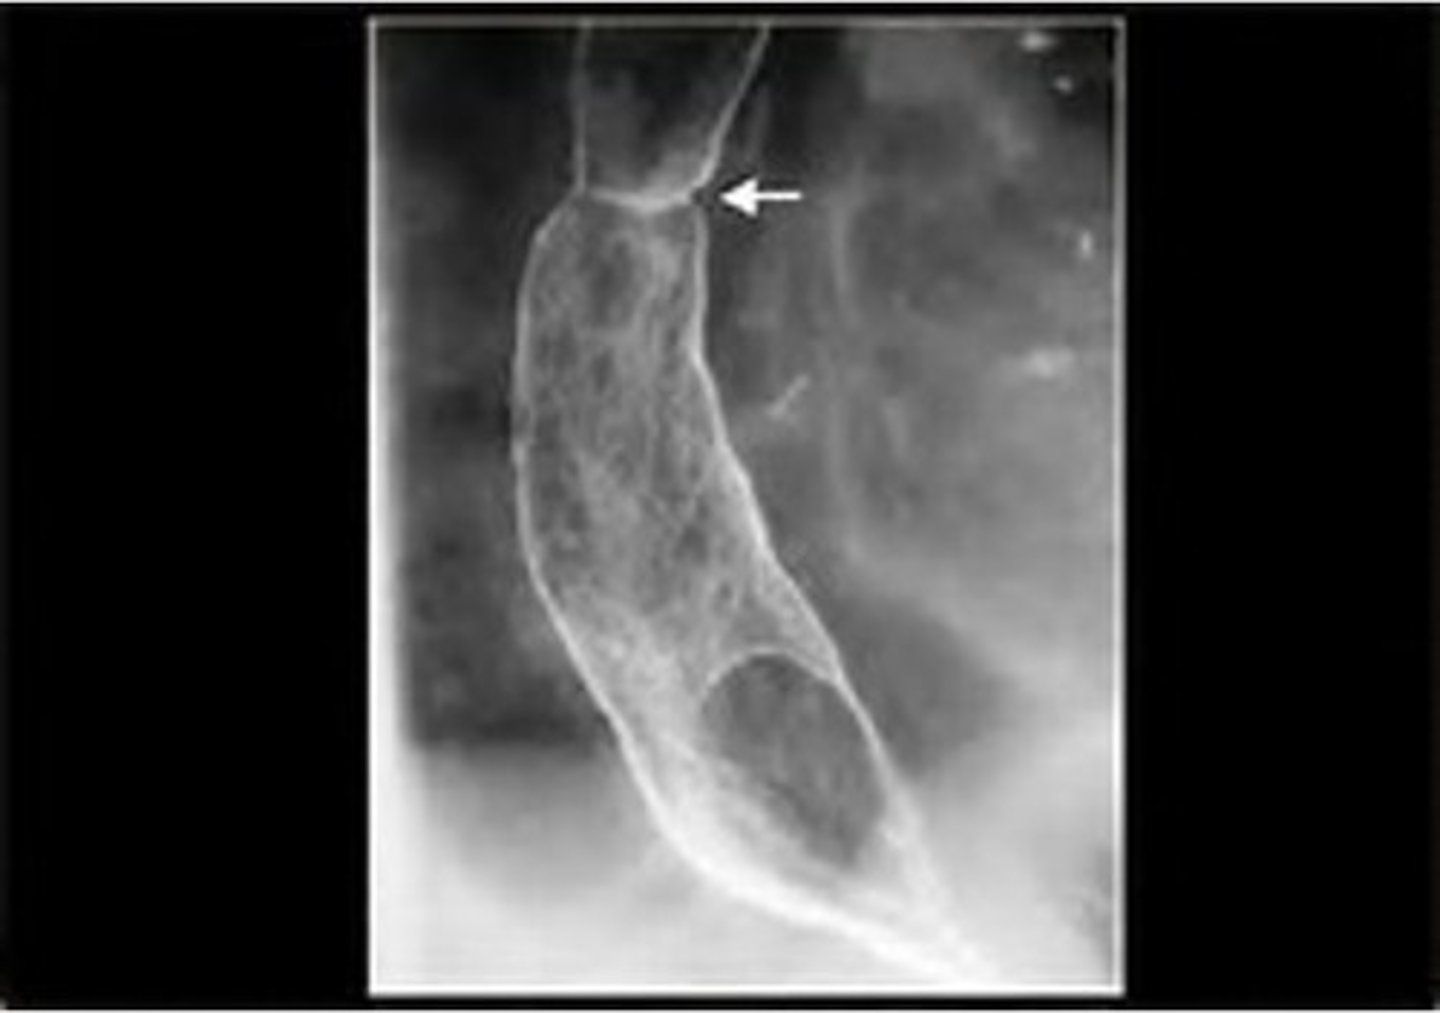

Achalasia

Achalasia (pic 5)

Achalasia (pic 2)

Achalasia (pic 3)

Achalasia (pic4 )